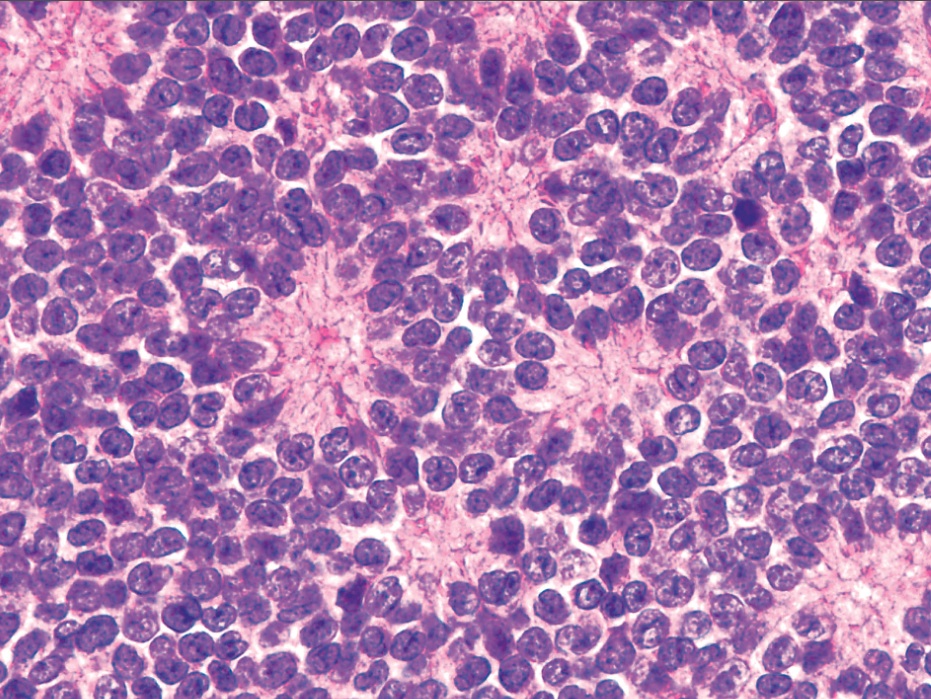

Microscopic (histologic) description

- Atypical Ewing sarcoma (Virchows Arch 2011;458:281)

- Nuclear enlargement

- Irregular nuclear contours

- Vesicular or coarse chromatin

- Prominent nucleoli

Microscopic (histologic) images